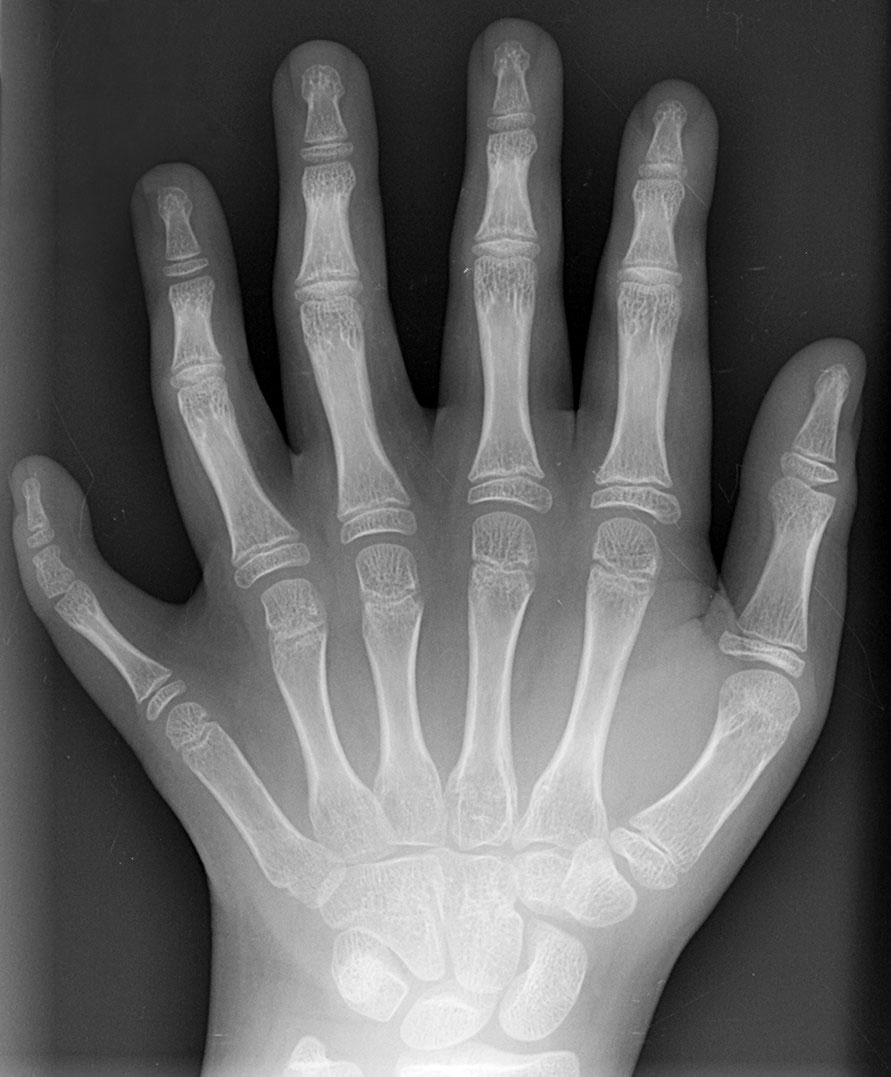

Figure-9.jpg

Figure 9. Our hands are striped. Polydactyly reflects a change in the underlying Turing pattern, based on timing in development (Wikimedia).